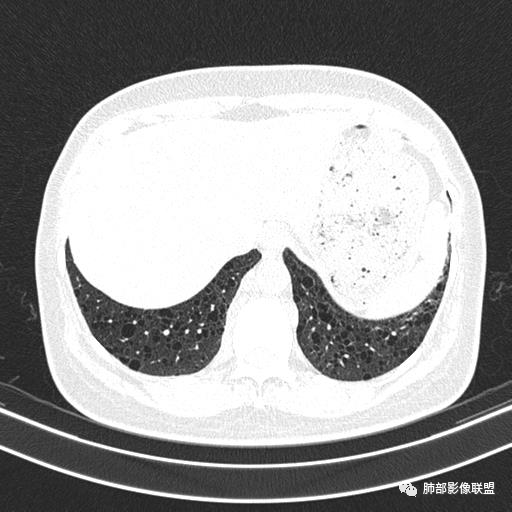

双肺弥漫囊腔,累及肋膈角,囊腔形态相对规则单一。

女,46,活动性气喘1年。苯吸入史半年。胸部CT:两肺弥漫囊腔,上至肺尖,下至肋膈角,形态类似小囊腔。考虑:LAM,鉴别LIP,BHD,PLCH等。

双肺弥漫大小不一薄壁含气囊腔,囊间肺组织正常,正常肺背景,肺尖肺底受累;青年女性,气喘,支持LAM

CT表现:双肺弥漫大小不等的薄壁囊腔,囊壁<2mm,外形规则,血管影多位于囊腔周围,囊腔之间肺组织正常,随着疾病进展到晚期,囊腔变大、增多,不可胜数,囊腔可融合成较大的囊,与肺气肿相似,形成间质性肺纤维化。部分病例可出现结节影。